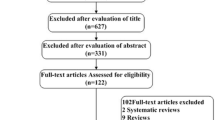

A total of 352 potentially relevant studies were identified, including 299 retrospective studies and 53 reviews/metanalysis (Fig. 2).